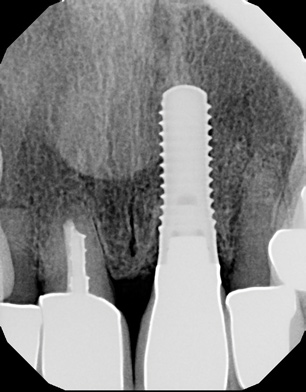

Fig 1. Pretreatment; a failed maxillary central incisor due to severe internal-external root resorption.

Figure 1

The patient, a healthy 45-year-old nonsmoking woman (American Society of Anesthesiologists [ASA] II), presented with a failed maxillary central incisor due to severe internal-external root resorption (Figure 1). She had a high esthetic risk profile based on 12 presenting esthetic risk factors (key No. 1), including a high lip line, high esthetic expectations, and adjacent teeth that had been restored (Figure 2).Site-specific CBCT (Carestream CS 9300, Carestream Dental, carestream.com) noted a thick intact buccal plate and a class 1 sagittal root position (Figure 3 and Figure 4). Preplanning with a bone-level 4.1-mm diameter x 14-mm long implant (Straumann Bone Level Roxolid® SLActive, Straumann, straumann.com) assured a 3-mm buccal gap upon placement and a screw-retained position (key No. 2). Prior to placement, intact buccal and palatal walls were confirmed. Figure 5 shows palatal wall placement of the implant after minimally traumatic flapless tooth extraction. An anatomically correct surgical guide template was used to assure a screw-retained position and correct vertical depth of approximately 4 mm from the mid-buccal apical extent of the guide template, which correlated to 1 mm apical of the intact buccal plate (key Nos. 3 through 5). The two-unit (8-9x cantilever) fixed provisional was recemented post-surgery. The 3-mm buccal gap was grafted tightly with a low-substitution DBBM (Bio-Oss®, Geistlich Pharma, geistlich-na.com) (key No. 6), and a pouch was created with a Buser membrane instrument (Hu-Friedy, hu-friedy.com) from line angle to line angle as a mini full-thickness flap to the mucogingival border to accept a connective tissue graft (Figure 6). The connective tissue graft, 1-mm thick x 12-mm long x 7-mm wide (Figure 7), was harvested from the palate (key No. 7).